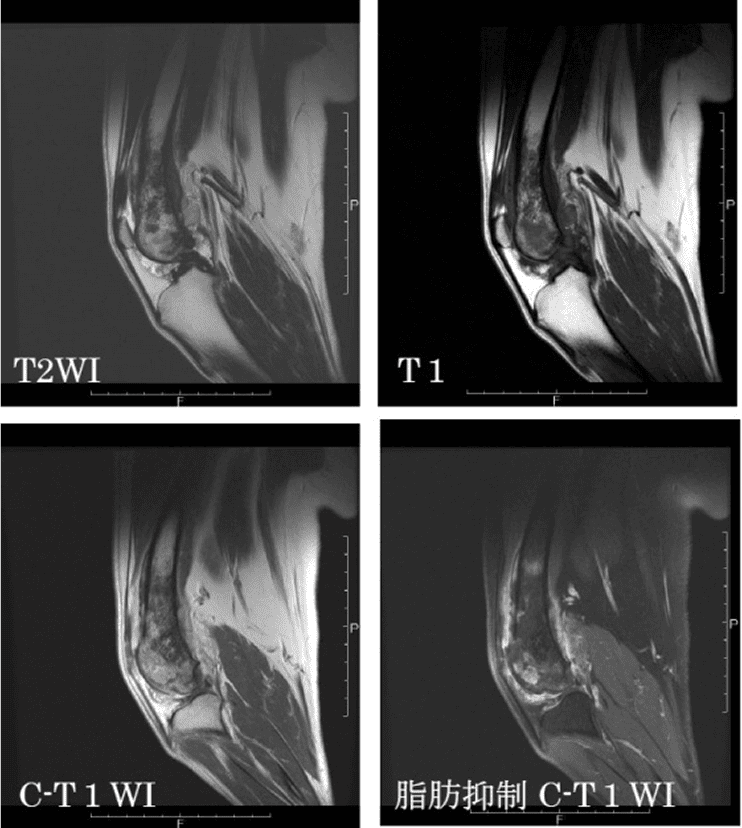

骨腫瘍